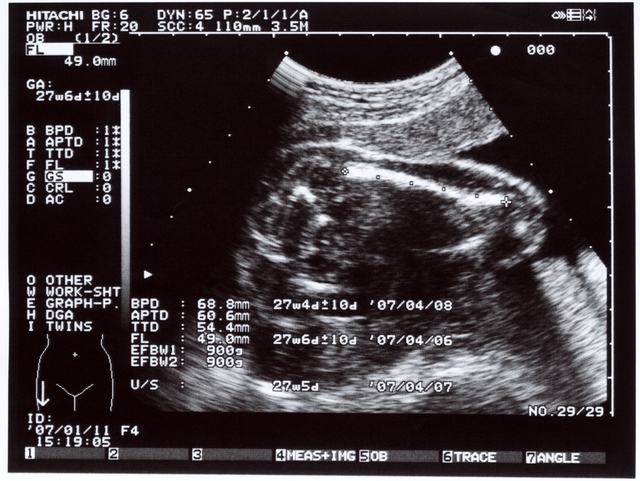

妊娠27週の赤ちゃんの状態|胎動やエコーで見える様子は?

赤ちゃんの器官発達

お腹の中の赤ちゃんは、目や耳の機能が完成します。まぶたが少し開くようになってくるので光の明暗を感じられます。

また、味覚が発達して苦味や甘味の区別がつくようになるので、産まれた後にママのおっぱいを探す準備をしているとされています。大脳皮質も発達してくるので、自分の意思で手や足を動かしたり、色々な感情が芽生えてきたりする時期でもあります。

聴覚も発達していて、感情も芽生えてくるため、ママやパパが声をかけてあげればお腹の中で喜びを感じているかもしれませんね。